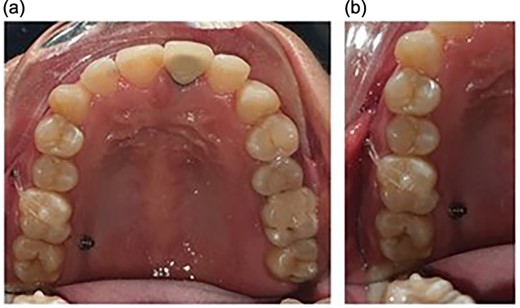

PLANNED MOLAR INTRUSION

Orthodontic miniscrews measuring 1.6 mm in width and 8 mm in length, respectively, were placed. The screw on the buccal aspect was placed between the maxillary first molar and second premolar, and the one on the palatal aspect was placed between the first and the second molar (Fig. 1). The placement of the screws was planned in order to have a diagonal coverage of the occlusally directed forces for intrusion.

Placement of the miniscrews: (a) on the buccal side between the second premolar and the first molar and (b) on the palatal side between the first and the second molars; composite button on the occlusal surface to direct the forces along the long axis.